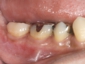

現在は、ドナーとなる歯の抜歯前に移植される側の処置を終了し、ドナーの歯を抜歯するとほぼ同時に、当院では3秒以内に受容側の中にドナーの歯を入れます。これはとても速いスピードであるといえ、このスピードで確実に行う為に、いろいろな研究を行い、CTスキャンのデータを応用した現在の移植のシステムを構築致しました。

このようにして移植された歯は、歯の根の表面にある歯根膜と言う組織がほぼ完全に保存され、生着(生きた状態で移植されて機能する事)する事によって、将来矯正治療で歯を移動する事もできますし、被せもの等を行えば全く移植歯である事は気が付かれないレベルで仕上がります。